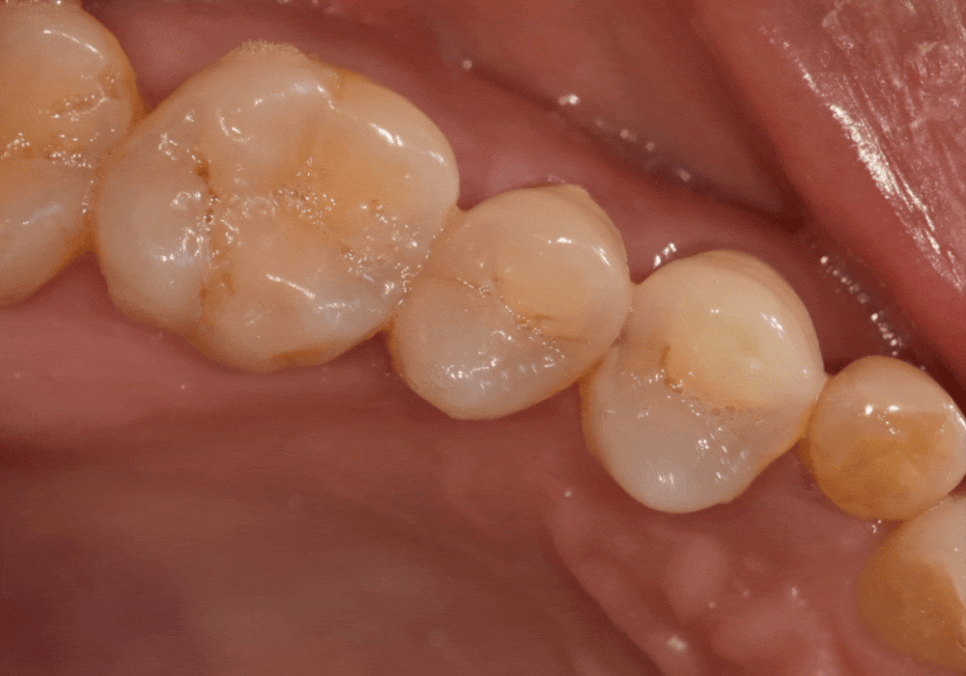

결과적으로 실제 가로폭은 좁지만,

260304

정면에서 보았을 때 ! 어떠세요?

그닥 작아보이지 않죠~

주변 치아와 자연스럽게 조화를 이뤄,

어색하지 않게 제작을 도와드렸습니다. ^^